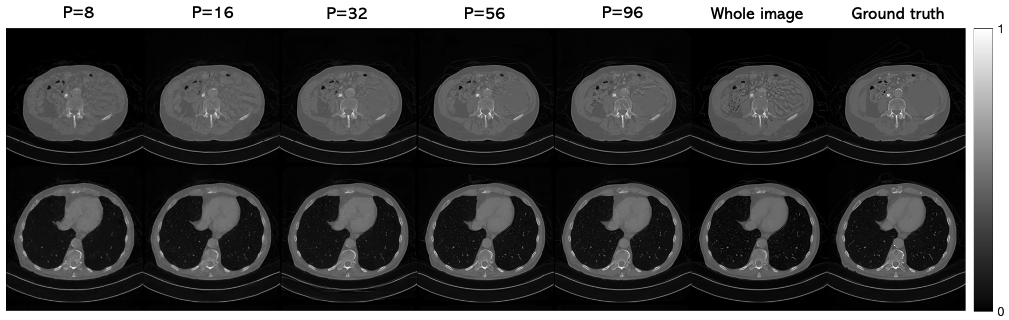

Effect of patch size.

We investigated the effect of the patch size PP used at reconstruction time for the 20-view CT reconstruction problem. We continued to augment the training with smaller patch sizes when possible so as to be consistent with the main experiments (patch size of 56 but also trained with patch sizes of 32 and 16), while using the same neural network architecture. Different amounts of zero padding were needed for each of the experiments per (3). App. A.4 provides the full details. At reconstruction time, the same patch size was used throughout the entire algorithm. Using a “patch size” of 256 corresponds to training a diffusion model on the whole image (without zero padding).

Table 5 shows that careful selection of the patch size is required to obtain the best results for a given training set size. If the patch size is too small, the network has trouble capturing global information across the image. Although the positional information helps in this regard, there may be some inconsistencies between patches, so the learned image prior is suboptimal although the patch priors may be learned well. At the other extreme, very large patch sizes and the whole image diffusion model require more memory to train and run. The image quality drops in this case as limited training data prevents the network from learning the patch prior well.

Figure A.5 shows the results of applying PaDIS to two example test images with different patch sizes. The main results, i.e., those shown in Table 1, used P=56P=56. For some of the other patch sizes, some artifacts can be seen in the images. Namely, the smooth parts of the image become riddled with "fake" features for small patch sizes and some of the sharp features become more blurred. The fake features in the right half of the image in the top row are especially apparent when applying the whole-image model. The runtime for different patch sizes were fairly similar, with P=8P=8 taking notably longer than the others due to the large number of patches required. The image size for these experiments was small enough so that the score function of all the patches could be computed in parallel; however, for larger scale problems such as high resolution 2D images or 3D images, large patch sizes become infeasible due to memory constraints.

Figure A.5: Results of PaDIS for 20 view CT reconstruction with different sized patches.